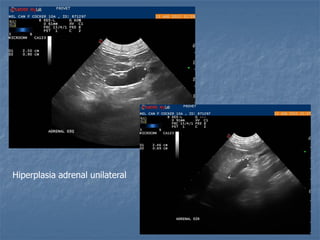

Hiperplasia adrenal unilateral

 Hiperadrenocorticismo  Hipofisáriodependente: há um aumento bilateral (80% dos casos!), pode ser simétrico ou assimétrico * Medida normal de espessura menor que 0,74cm cães adultos